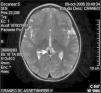

Con la sospecha de pubertad precoz se realiza radiografía de la mano-muñeca izquierda, que muestra una edad ósea de 5 años. Asimismo, se realizó una ecografía pélvica en la que se evidenció un útero de 35mm con línea endometrial visible y ovarios sin quistes ni tumores. Finalmente, la realización de un test de estimulación con hormona liberadora de hormona luteinizante (test LHRH) confirmó el origen central de la pubertad: pico de LH de 50,9 mUI/ml y pico de hormona foliculoestimulante (FSH) de 19,4 mUI/ml. Con el diagnóstico de PPC y con el fin de descartar patología orgánica cerebral, se solicitó una resonancia magnética (RM) craneal en la que se visualizó un quiste de la glándula pineal de 0,8 × 0,6cm (fig. 1), sin evidenciar signos de hipertensión intracraneal. El estudio de marcadores tumorales en sangre (α -fetoproteína y β -HCG) fue negativo. Tras 3 meses de seguimiento bajo terapia con triptolerina en dosis de 100μg/kg, la velocidad de crecimiento se había estabilizado, así como el grado de telarquia, sin presentar clínica neurológica alguna.